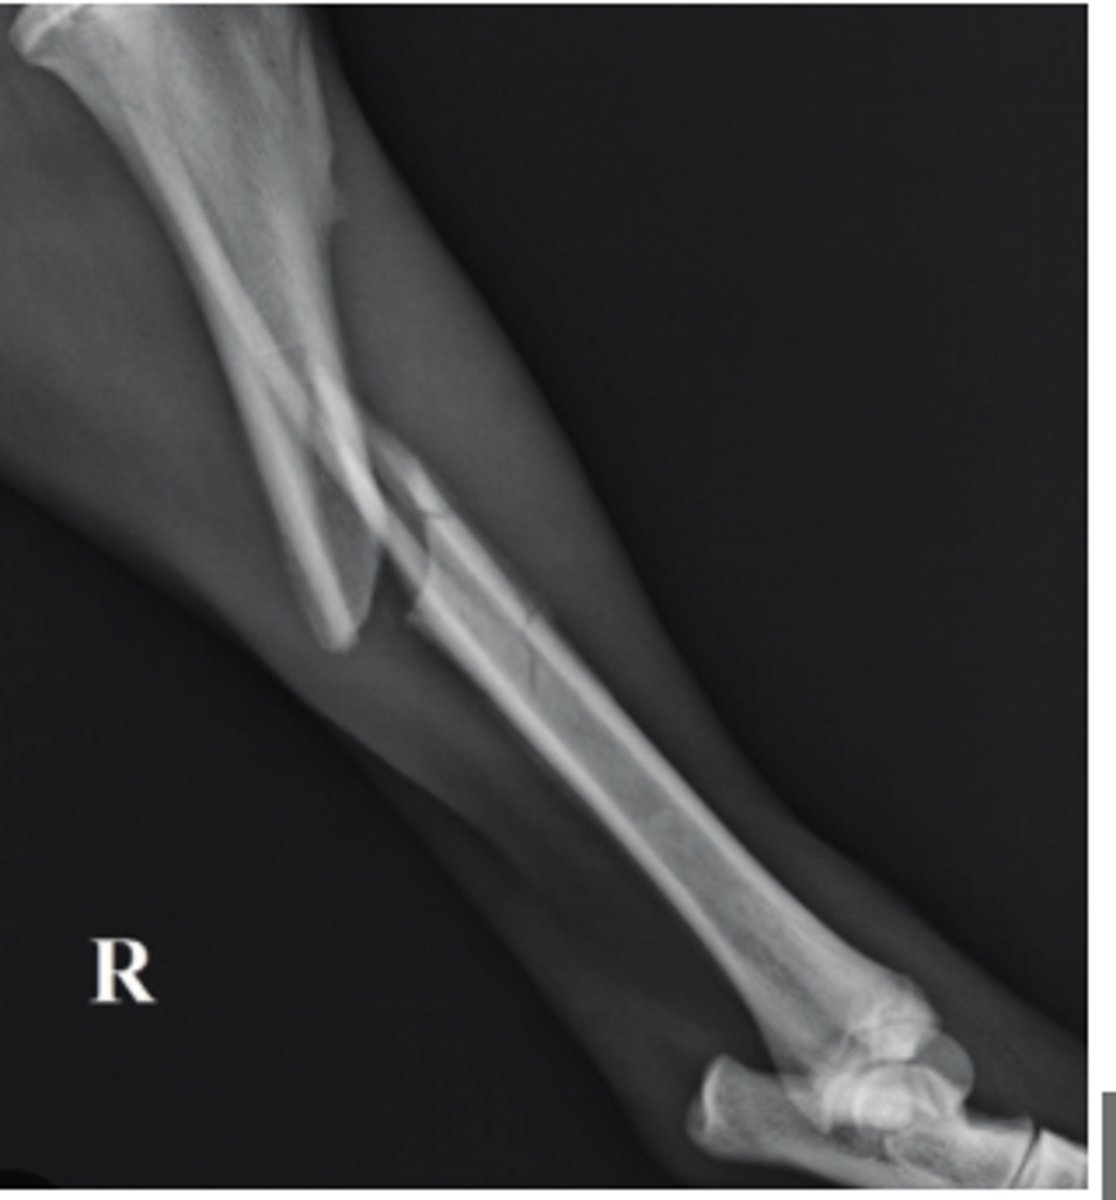

Panosteitis

10 y/o German Shepherd comes in with lameness on the right hind leg; what is the radiographic finding?

Primary bone tumor

6 y/o dog lame on the limb shown- what kind of tumor is this?

What radiograph condition a result of premature physeal closure?

Ill-defined margins

Irregular periosteal proliferation

Cortical lysis

Define an aggressive bone lesion?